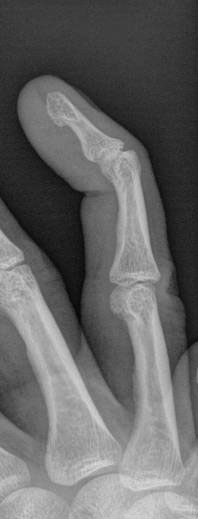

So heres what the finger looks like:

Typing totally sucks and I’m all splinted up for 8 weeks!